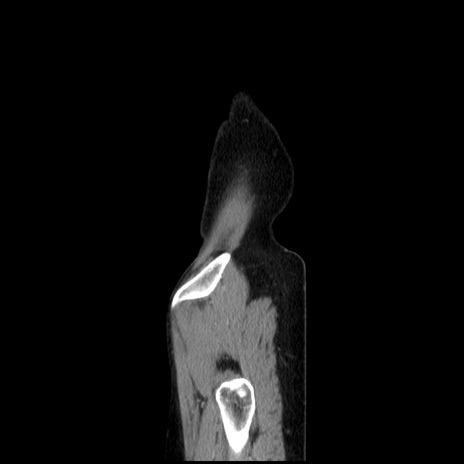

横断像

【症例】40歳代 女性

【主訴】上腹部痛、嘔気・嘔吐

【現病歴】約9時間前頃から急に上腹部痛、嘔気、嘔吐が出現。改善しないため救急要請。

【既往歴】子宮頚癌(広汎子宮全摘術、放射線療法)、腸閉塞

【身体所見】腹部:平坦、軟、腸雑音亢進、上腹部を中心に腹部全体に圧痛あり。

【データ】WBC 8400、CRP 0.03